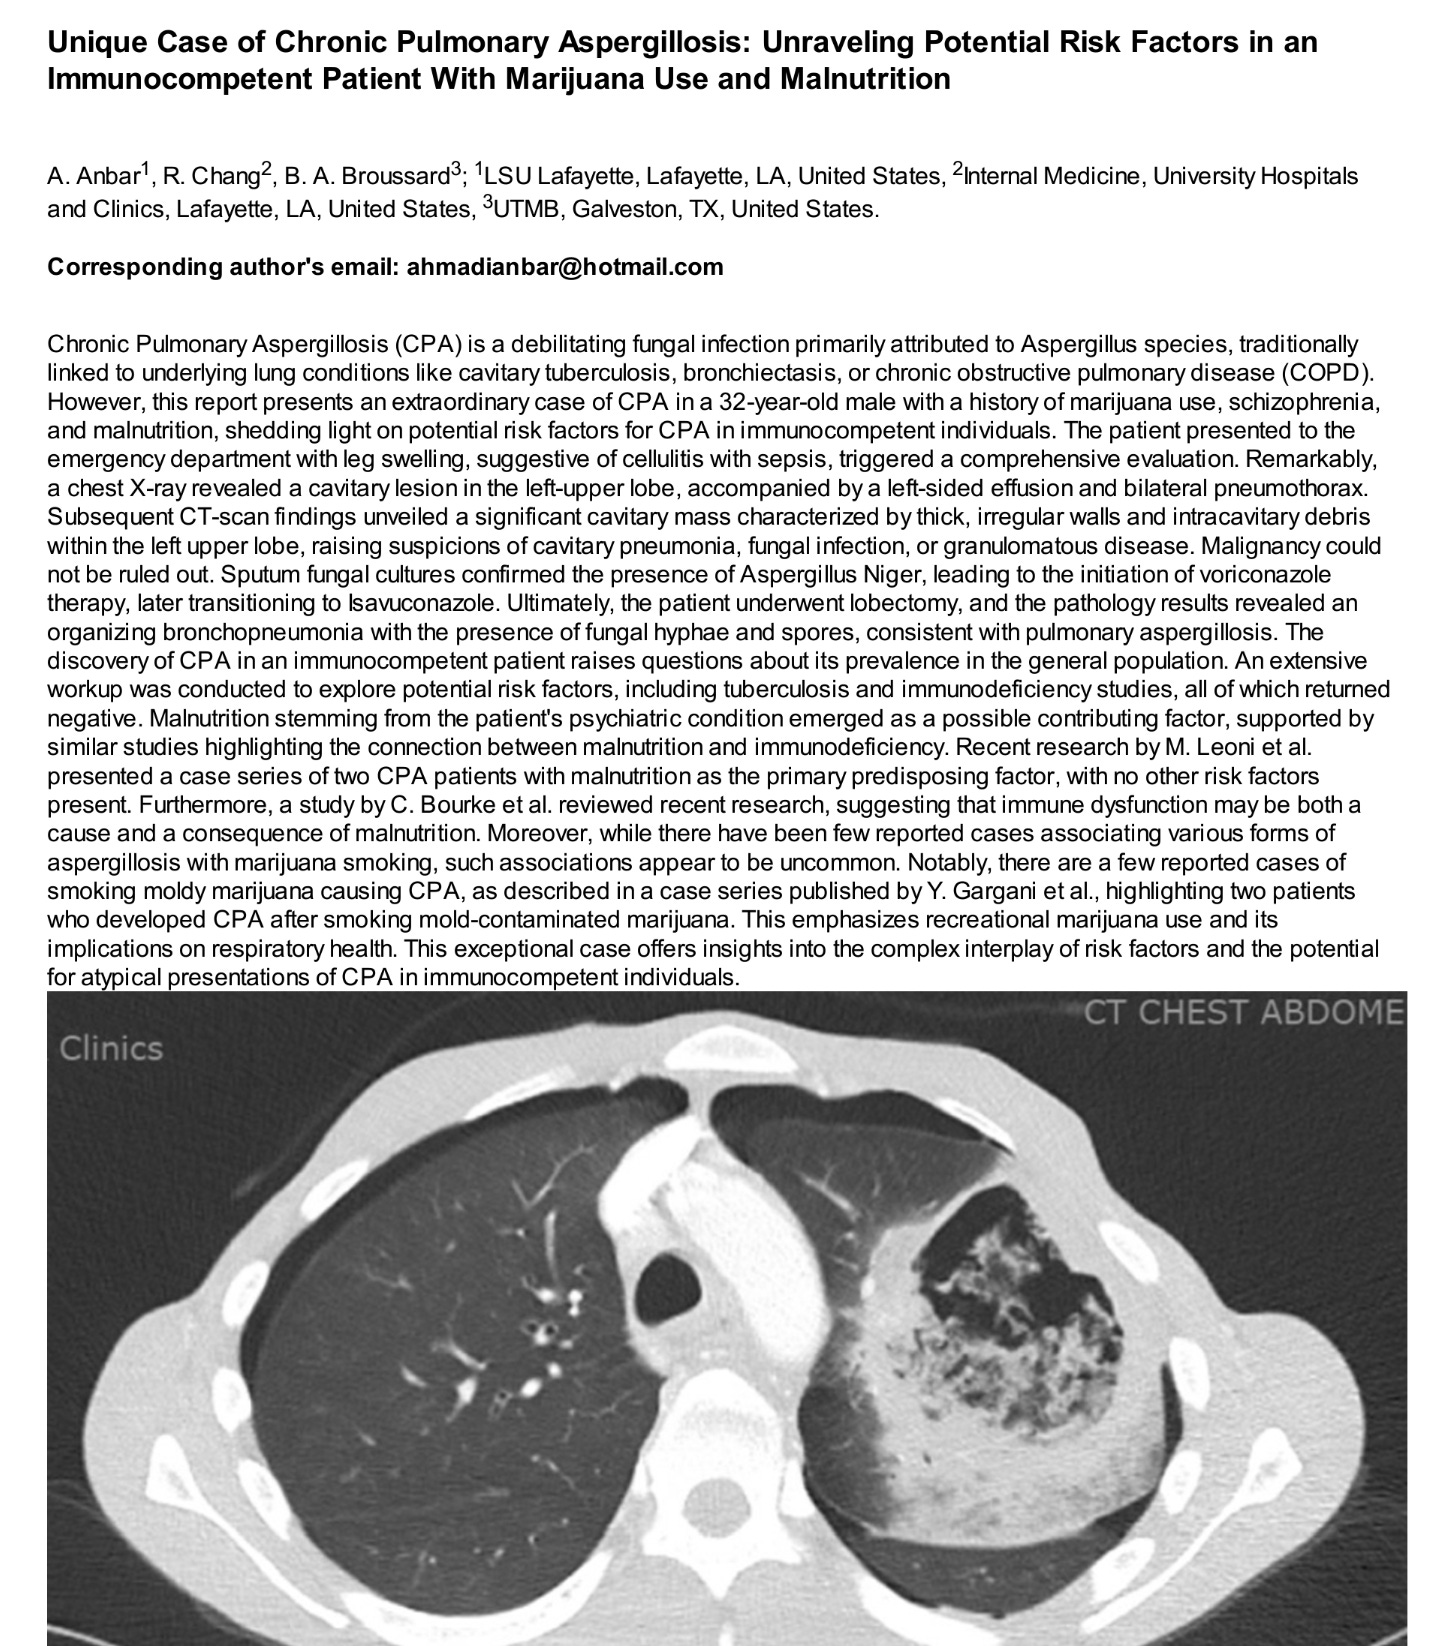

A May 2024 case report of Aspergillosis associated with Cannabis use. Lung Lobe removed.